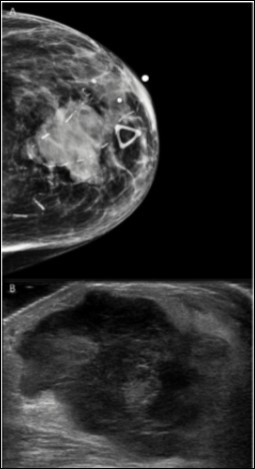

We report the case of a breast melanoma in a 75-year-old woman with a cancer history significant for ampullary adenocarcinoma for which she underwent surgery and chemoradiation approximately 9 years earlier. She presented to her oncologist with a left breast lump which appeared suddenly. There was no axillary lymphadenopathy. Diagnostic ultrasound and mammography revealed a 3.3 cm solid mass at 12 o’clock deep to the areola which approached the skin (Figure 1). Fine needle aspiration was performed at that time which was positive for malignant cells, consistent with a high grade sarcoma or spindle cell type carcinoma (Figure 2A,B). The malignant cells were focally positive for GATA3 and negative for ER and PR, and this was thought to represent a primary breast cancer. A metastasis from her ampullary adenocarcinoma was ruled out immunophenotypically. The patient chose to undergo mastectomy for definitive diagnosis and treatment.

Figure 1.Radiological Findings. Radiographic imaging of the breast revealed a heterogeneous, hypoechoic solid mass with vascularity measuring 3.3 cm with associated thickening of the skin. A. Tomography, B. Ultrasound

Radiological Findings. Radiographic imaging of the breast revealed a heterogeneous,                     hypoechoic solid mass with vascularity measuring 3.3 cm with associated thickening of the skin. A.     Tomography, B. Ultrasound